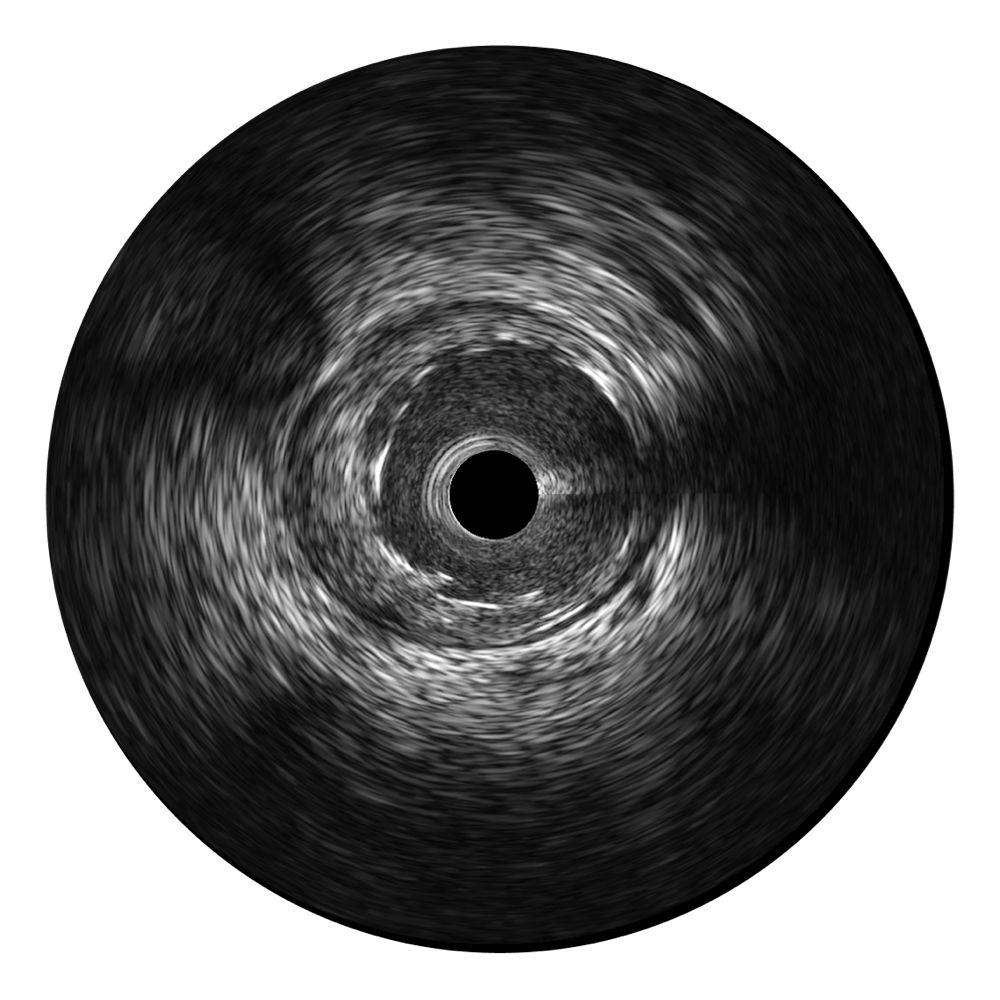

• 亚星官网宽频IVUS图像

对比传统IVUS导管成像,亚星官网宽频IVUS图像的近场支架梁显影更细腻,远场中膜外血管仍清晰可辨,兼顾远中近,兼顾分辨力与穿透深度